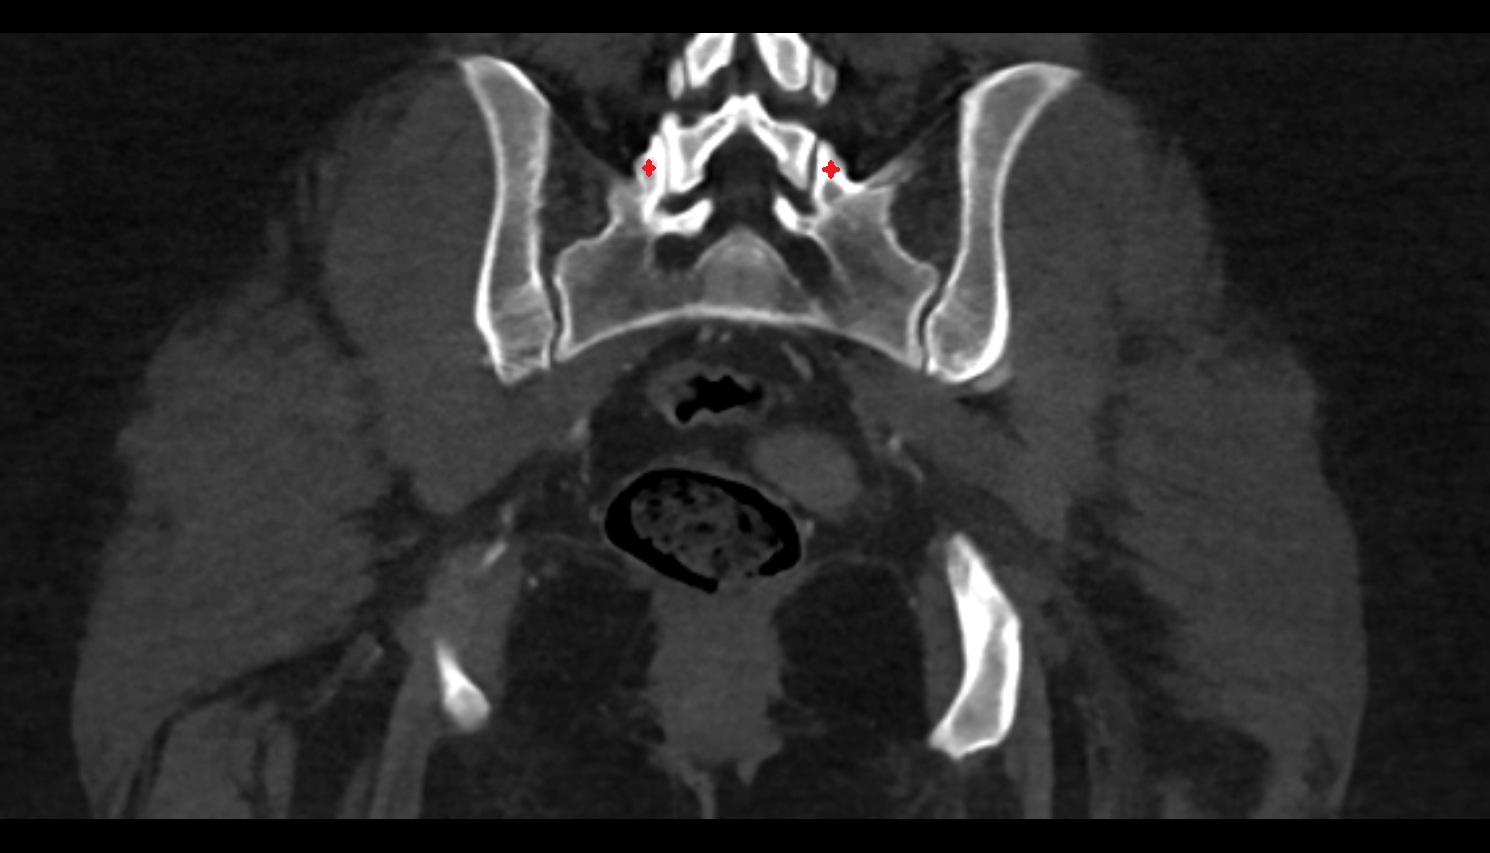

- Sacroiliac joint